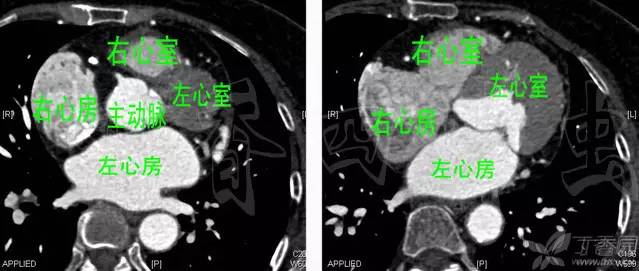

心脏分为左房、右房,左室、右室,当中有房间隔、室间隔。这个就潜意识里给我们对称的暗示,但是从正面视觉角度上看心脏的左房右房,左室右室,表现的相当不给力,不但形态上不对称,连位置都不对称。无图无真相,那好上图。

选择一个屌丝,脱光,取菜刀一把,在双乳头连线的高度,与水平面呈 30 度角度,手起刀落(记住要干净利落不能拖泥带水),就是如上视觉效果。

这个就是心脏最漂亮切面——心脏四腔切面,关于四腔切面,之后推出的心脏超声切面解剖会详细提到,在这里我们要注意的是室间隔所在平面应该与矢状面(xy 轴平面)呈 45 度左右角度。

如果从正面上观察这个心脏,室间隔几乎是横在我们面前遮挡住整个左心室,只留下少许心尖部能看到。在我们正面看到应该是整个右心室,而左心房它完全是在心脏正后部,再往后就是食管、气管、脊椎。因此称右心室为前心室,左心房为后心房似乎更为恰当,它们位置上前后对称,而右心房和左心室称呼勉强合格吧,它们左右对称。

有了正确的心脏观我们就不会在 CT 片上的左侧去寻找左心房、右侧去寻找右心室,如图。